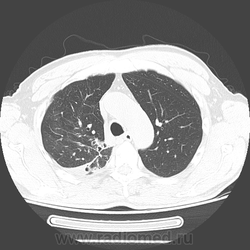

60 лет. В 1972 году верхнедолевая лобэктомия по поводу кавернозного туберкулеза.

Месяц назад появилась слабость, колящие боли под лопаткой, температура тела до 40 градусов, одышка. Вызывал скорую помощь, что-то делали, не помнит... Назначили АБ, на фоне лечения температура 40 днем, 38 вечером держалась неделю, потом постепенно становилось лучше...

Сейчас кашель, желтоватая мокрота, бывали с примесью крови. Температура сейчас ближе к норме.

Направлен с диагнозом: внебольничная субтотальная пневмония, осложненная сухим абсцессом? туберкулез?

С учётом всёй имеющейся информации, больше данных за абсцедирующую пневмонию. Подобная "сухая" полость, довольно нехарактерна для банальных пневмоний, а так же с учётом перенесённого туберкулёза в анамнезе, последний никак нелья исключать из дифряда. Можно сказать, что полость по скиологии очень похожа на симтом "перстня "- признак периферического рака, не исключается вариант сочетания последнего с пневмонией. И как всегда...перед нами встают три "кита"-пневмония, туберкулёз и рак!

Нужны все рентгенограммы, все анализы мокроты - хоть какое-то подспорье. Я бы написала так: с учетом отсутствия (не увидела) очагов отсева, лимфангита, более вероятен исход абсцесса в сухую полость, диф.диагноз с тбс и полостной формой рака. Думаю, что только оперативное лечение и последующая гистология даст верный ответ.

"Грибы" не стоит исключать из диф ряда. Но всё-таки стенки ен такие и тонкие, есть специфические локальные утолщения, виден симптом "перстня", наличие матовости дистальнее, более вероятно, полостная форма периферического рака. А грибы присоединились позже. Когда последний раз флюорографию проходил?

Полостная форма грибов - редкость..., особенно при актиномикозе. А при аспергиллезе - одна полость? и такая температура? Если думать про аспергиллез, то уж о поселении его в существующей полости... Но как-то не впечатляет! Хочется всё свести к острой инфекционной деструкции и формированию сухого абсцесса... Но откуда участки матового стекла нарисовались + в противоположном легком?

Единственное, что до сих пор смущает - лобэктомия. Что-то не сильно выражено ремоделирование правого лёгкого при резекции такого объёма ткани. И не даёт покоя междолевая плевра справа на сагиттальном скане - похоже, главная...

Лобэктомии тоже не заметил, но здесь есть еще бронх справа, который отходит до бифуркации. Тут максимум нет одного сегмента. В заключении обтекаемо написал что более вероятно дренированному абсцессу вследствие деструктивной пневмонии, либо полости с грибами. По клинике и лаборатории посмотрел еще когда поступал - практически ИТШок.

Я бы на первое место поставил абсцесс, но не стал бы исключать полостную форму рака. Хотя яркая клиника склоняет к первому. На туберкулез не очень-то похоже.